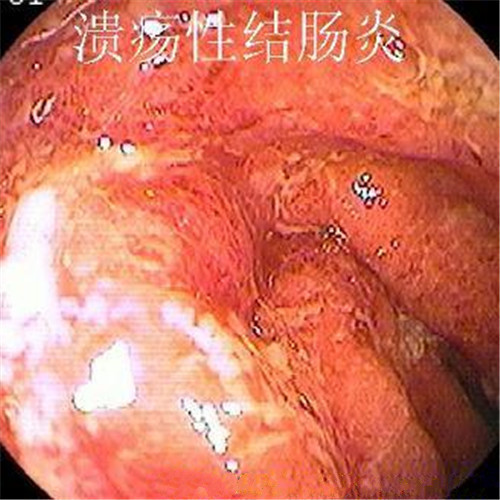

潰瘍性結腸炎的病理

潰瘍性結腸炎重度糜爛